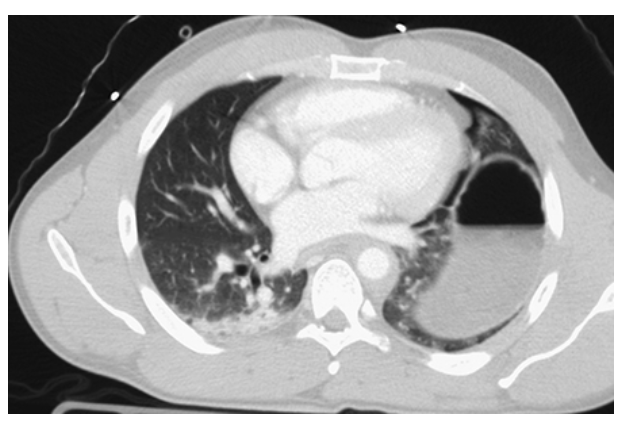

Lung Contusion. CECT axial images of a trauma patient showing the extensive pulmonary contusion of the right upper and lower lobes. There is confluent lung opacification with multiple small posttraumatic pneumatoceles.